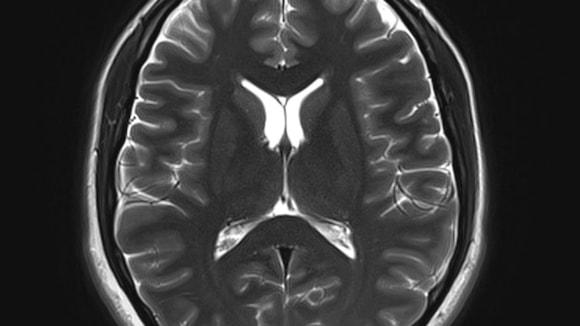

The team from the Universities of Edinburgh and Dundee, has approval to use a unique, large data set made up of CT and MRI brain scans from patients in Scotland from 2008 to 2018, representing 1.6 million images.

The team will use artificial intelligence and machine learning to analyze the image data alongside linked health records such as demographics and treatment history, without patients being identifiable, to find patterns that could indicate a person’s risk of developing dementia.

The ultimate aim is to build a digital healthcare tool that radiologists can use when scanning for other conditions to determine a person’s dementia risk, and to diagnose early stages of related diseases, such as Alzheimer’s.